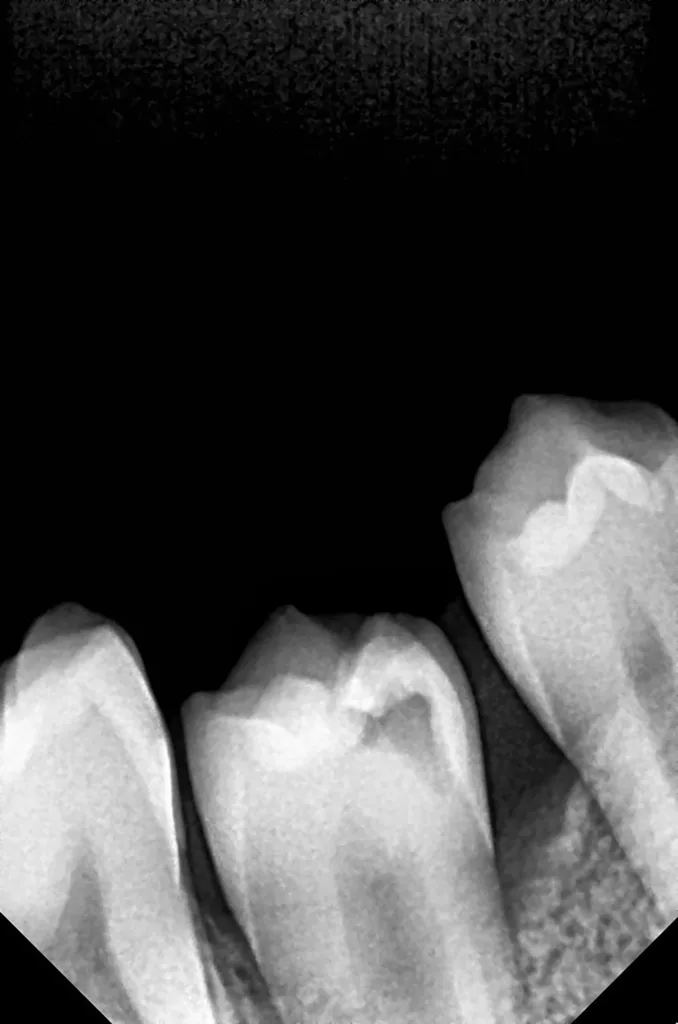

Bei routinemäßigen Röntgenkontrollen ergeben sich manchmal Zufallsbefunde unklarer Genese. So stellt sich beispielsweise bei der Betrachtung der Abbildung 1 die Frage, wie sich ein Zahnhartsubstanzdefekt so schnell entwickeln konnte. Ein weiteres Röntgenbild (Abb. 2), das vor dem Zahndurchbruch aufgenommen wurde, zeigt jedoch, dass es sich in diesem Fall nicht um Karies, sondern um die sogenannte präeruptive intrakoronale Resorption (PEIR) handelt. Für diesen Befund finden sich in der Fachliteratur auch noch andere Bezeichnungen wie „idiopathic external resorption of unerupted permanent teeth“ [1], „intra-follicular caries“ [2], „radiolucent lesions resembling caries“ [3], „occult caries“ [ 4] oder „pre-eruptive caries“ [5].

V. Slabkovskyi, O. Liutikovwährend des Durchbruchs des Zahnes 36.

Das fünfjährige Mädchen stellte sich 2017 zur jährlichen Routinekontrolle vor. Im Rahmen der Untersuchung wurden Röntgenaufnahmen der Milchmolaren gemacht (Abb. 2). Der klinische und radiologische Befund der vor uns früher gelegten Kompositfüllungen war gut, es wurde allerdings eine PEIR an den noch nicht durchgebrochenen ersten bleibenden Molaren festgestellt (Abb. 2). Den Eltern wurde empfohlen, sich unverzüglich bei Beginn des Durchbruchs der ersten Molaren erneut zur Behandlung vorzustellen. Ein Jahr später erschien die junge Patientin schmerzfrei zur Kontrolle. Der Zahn 36 war noch teilweise mit Gingiva bedeckt. Auf einer neuen Röntgenaufnahme (Abb. 1) wurde die PEIR-Läsion mit unveränderter Größe in pulpanahen Bereichen bestätigt (Grad 3 der Läsion nach Seow). Der Zahnschmelz sah intakt aus, es konnte kein pathologischer periapikaler Befund bei den noch nicht ausgewachsenen Zahnwurzeln festgestellt werden. Daraufhin wurden die verschiedenen Behandlungsmöglichkeiten von Fissurenversiegelung bis Vitalerhaltung der Zahnpulpa mit den Eltern des Kindes besprochen.